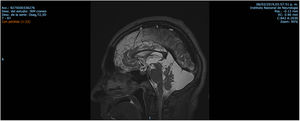

Patient 3 is a 45-year-old male who noticed unsteadiness and frequent falls from age 10. His symptoms were progressive, and he used a walking aid. On examination, his speech was slurred but intelligible. Hoffman and Trömner signs and exalted patellar reflexes, and spasticity of the lower limbs were present. Bilateral Achilles reflexes were abolished. The patient complained of leg paresthesia, numbness, and cramps. Abolition of deep sensitivity was evident from the knee downwards (Table 1). MRI findings (Fig. 6) were similar to his brother's (Patient 2).

| Patient 3 (Family 2) | M | 45 | 10 | Ataxia, mild cognitive impairment, spasticity, slurred speech, pyramidal syndrome, decreased sensitivity in distal extremities | Cerebellar and cortical atrophy, retrovermian arachnoid cyst similar to brother Fig. 6 |